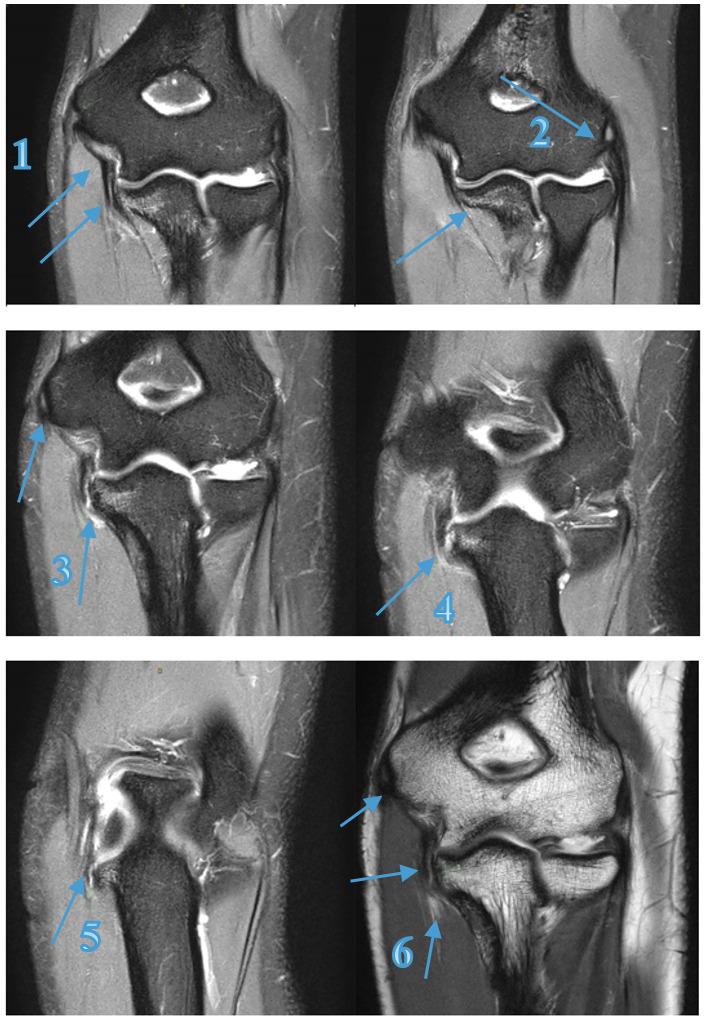

Athlete A

A 21-year-old elite male Javelin thrower (Australian representative) presented with right sided medial elbow pain, rating up to 8/10 (NRS), with a history of right medial elbow issues including medial epicondylitis and FCU tendinosis. The physical examination findings were primarily palpatory tenderness at the UCL over the joint line (oblique ligament location) and at the sublime tubercle attachment, positive orthopaedic tests for the shoulder and elbow, with changes in the elbow extension (160°), shoulder flexion (150°) and abduction (160°) and internal rotation (IR) (55°) (Table 2). The athlete only experienced pain in posterior medial elbow when throwing at high intensity or when in full elbow flexion during the catch phase of an Olympic clean exercise. Because the athlete was unable to compete at an elite level seven weeks post symptom onset, he was referred for a magnetic resonance imaging (MRI) scan of the right elbow, which revealed a high grade UCL tear with a small associated avulsion fracture with no ligament displacement (Figure 2). Subsequent consultation with an elbow orthopaedic specialist recommended surgery on the ligament however athlete, coach and chiropractor all agreed to attempt conservative therapy.

A 17-year-old amateur male Javelin thrower (State Representative) presented with right elbow pain which occurred during a competition 4 days prior. He described an audible pop and sharp pain experienced just before releasing the javelin. In the six weeks prior to the competition, the athlete experienced minor discomfort 3/10 (NRS) in the shoulder and medial elbow, which would ease at the completion of training and competition. As presented in Table 2 the physical examination findings, there was obvious swelling and palpatory tenderness over the medial elbow joint line (UCL/FCU & FDS tendons) and the medial epicondyle. The medial elbow dysfunction was exacerbated by any gripping or pronation motion reporting an 8/10 (NRS) at worst, reducing to 4/10 with the influence of ice, anti-inflammatories and analgesics as presented in Table 2 and 3. All activities ceased immediately until the pain and swelling was reduced. Due to the mechanism of injury and clinical findings, the practitioner referred him for MRI (Figure 3) which revealed a full thickness tear to the anterior bundle of the UCL with a low-grade partial tear of the FCU muscle, distal to the common flexor origin, which dictated the treatment choices and future modification to the training program.

The initial phase of Athlete A’s treatment and rehabilitation schedule was initiated with training modifications based on symptoms, with the goal of competing at week 6, as outlined in Appendix A and Appendix B. This was unsuccessful resulting in a complete remodel of the treatment and training program based off further investigation (MRI - Figure 2) and surgical opinion. After altering the treatment (Appendix A), rehabilitation, and training (Appendix B) over a 15-week period, the athlete rated “Excellent”37 Conway Scale (Table 3) and returned to high level competition at week 24 with a throw of 99.46% of previous personal best (PB) 76.34m (800g) and at week 27 a throw of 78.75m (800g) 3% greater than the previous PB.

MRI has typically been the gold standard imaging modality in identifying tendon and ligament pathology such as UCL injuries, particularly when full-thickness tears are present.10,51,52 Athlete A’s UCL injury was diagnosed by physical examination and confirmed by MRI (Figure 2), and Athlete D (Figure 3) also had diagnoses confirmed by MRI.